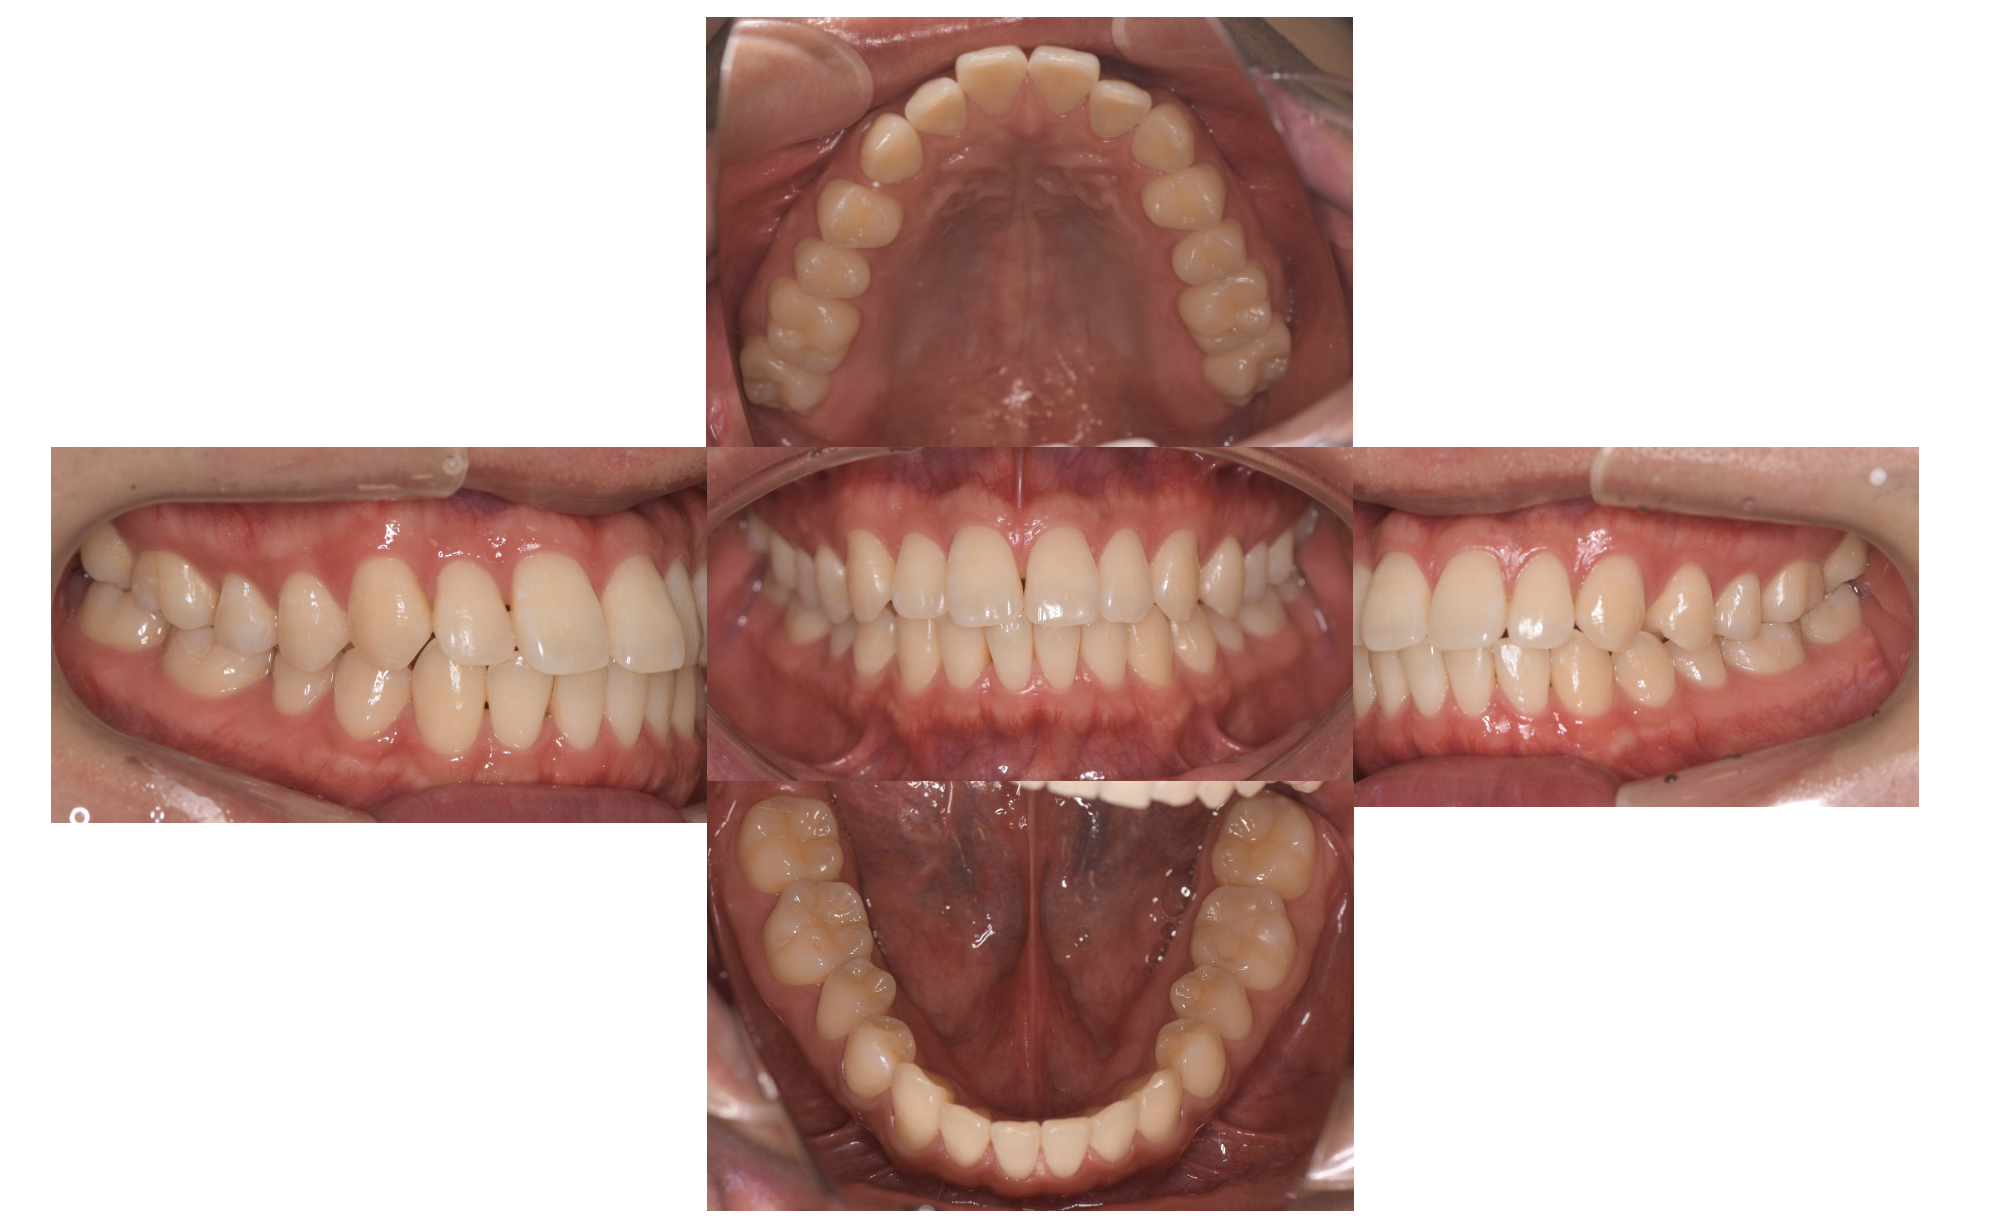

治療前

噛めないということを主訴にご来院されました。ただパッと見るとどこが噛んでいないのだろうと言うくらい綺麗な歯をされています。デンタルドックによる精密検査の結果、動画で解説しているように、口腔内写真をみると歯に隙間があったり、所々咬んでいないところも確認できます。ただし口腔内写真だけでは、どの歯がどのように、どんな強さで当たっているのかがわかりません。